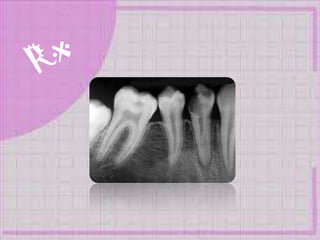

“Enfermedad multifactorial

infecto-contagiosa que afecta

los tejidos duros del diente”